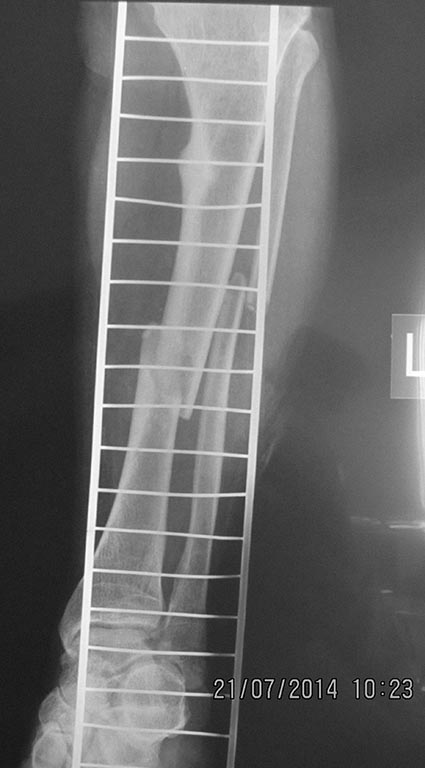

Re: перелом бедра с исходной деформацией

Выкладываю, как и обещал. За репозицию педплечья не осуждайте!